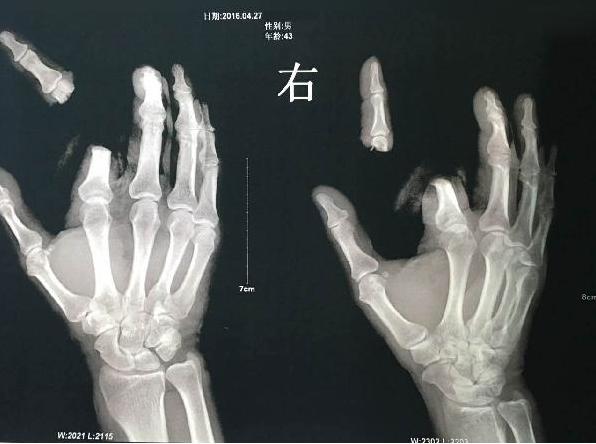

谣言的伤疤:谣言常德一男子轻信隐翅虫剧毒谣言 挥刀斩断食指

这是腾讯2016年的真实报道

报道称,湖南省常德市澧县一男子用手指将一只隐翅虫碰碎,不慎沾上少许毒液。

想到自己看到的有关隐翅虫毒液可轻易致人死亡的文章,觉得自己也出现了类似的症状。情急之下,该男子竟拿起菜刀将自己右食指砍下。